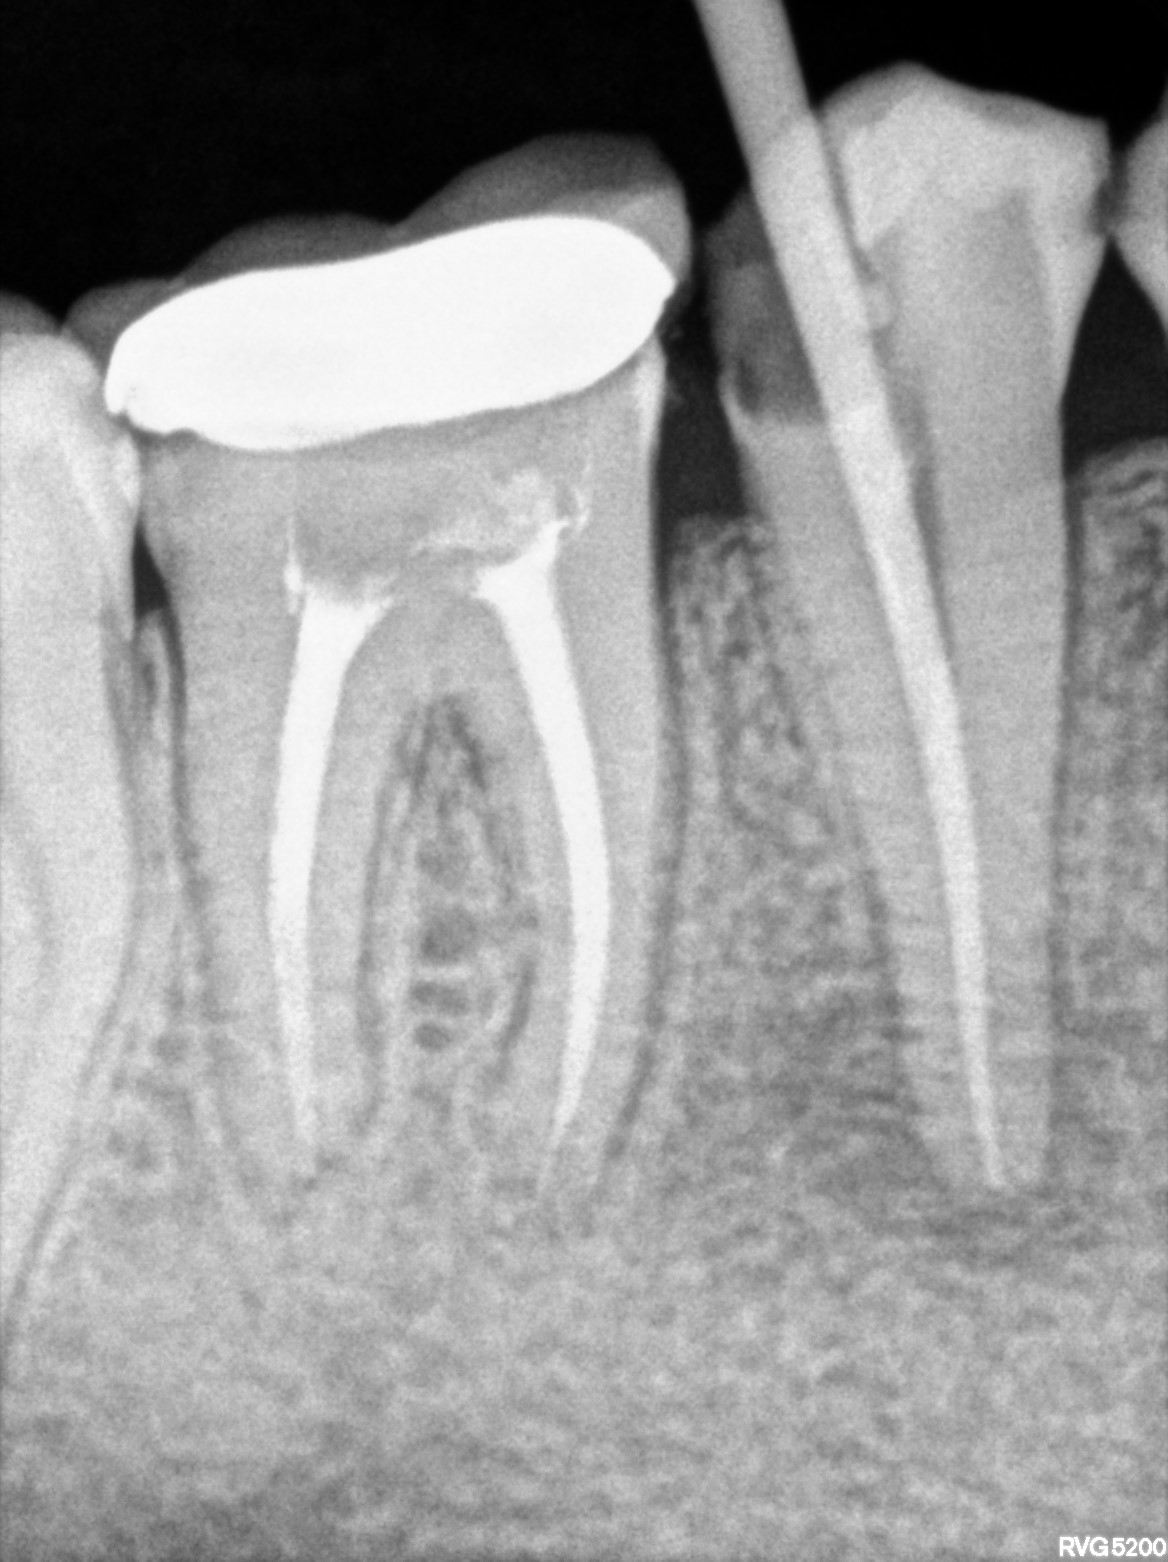

Dental Radiographs FHIR: DocumentReference · LOINC 24641-7

R55.jpg

24641-7

| Root canal treatment | 234780006 | D3330 Endodontic therapy, molar tooth | ##46 | 2026-03-04 | completed | obt 46 | |

| 2026-03-04 20:27 | fulfilled | obt 46 — Dr Riyaz | |